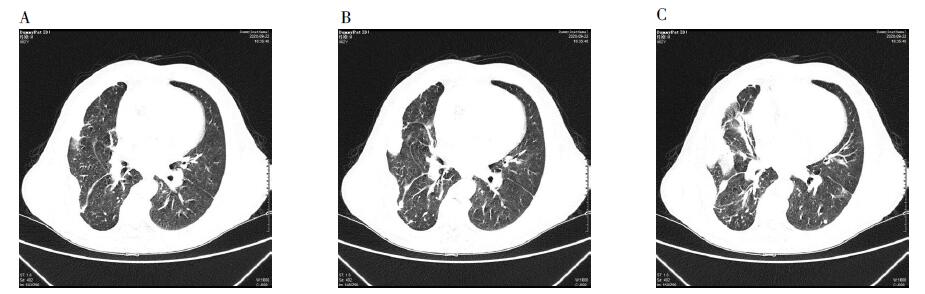

Lophomonas blattarum infection is rare in outpatients, which is easily to be overlooked. This article briefly introduces the symptoms of an infected person, the examination, differential diagnosis and treatment measures that we have taken for clinical reference. The patient is male, 62 years old, long live and work in Ganyu district, Lianyungang. On September 15, 2020, the patient developed fever, expectoration after the rain, and fever regression after self-medication. Three days later, he developed fever again, accompanied by pain in the right flank, and went to Ganyu District People's Hospital for treatment. With WBC 19.74×109/L, N 83.7%, hypersensitive C-reactive protein 33.19 mg/L; CT showed inflammation in the middle lobe of the right lung and two lower lobes, and effusion in the right pleural cavity. The hospital gave anti-infection and phlegm treatment for 3 days, but the effect was not good. On 22nd, he was transferred to Jiangsu Hospital of Traditional Chinese Medicine. The blood routine showed hypersensitive C-reactive protein 65.8 mg/L, WBC 11.66×109/L and E 6.9%. CT showed multiple nodules and patchy shadows in both lungs. Lung function showed decreased pulmonary ventilation function. Fibrobronchoscopy revealed the presence of infection. Meanwhile, the fibrobronchoscope lotion was sent to Nanjing Center for Disease Control and Prevention for parasitological examination. The hospital considered pneumonia and gave anti-fungal and expectorant treatment for 3 days, but the effect was not good. At this time, Nanjing Center for Disease Control and Prevention reported positive Lophomonas blattarum test results. The hospital then added ornidazole treatment, one week later, the patient's fever, cough, chest pain and other symptoms disappeared, related infection indicators returned to normal, recovered and discharged. In this case, the patient was treated with antibiotics successively in two hospitals according to the experience of clinicians, but the effect was not good. Ornidazole treatment was timely adopted after the identification of Lophomonas blattarum (at the same time, attention should be paid to the identification with the bronciliated columnar epithelial cells), and the effect was significant, and the symptoms soon disappeared. It suggests that it is very important for clinicians to use targeted treatment for pathogens. Lophomonas blattarumis rare in patients with clinical infection and lack of detection means, so it is easier to miss diagnosis, so vigilance should be taken.

2020年9月22日转至江苏省中医院后, 完善相关检查。血液:超敏C反应蛋白65.8 mg/L, 白细胞计数11.66

根据以上结果, 该院考虑社区获得性肺炎, 隐球菌感染的可能, 遂给予伏立康唑抗真菌, 痰热清静滴+盐酸氨溴索静滴+复方薤白胶囊口服化痰治疗3 d, 患者自觉效果不明显。9月25日南京市疾控中心反馈寄生虫检测结果示:蠊缨滴虫阳性。该院遂加用奥硝唑抗滴虫治疗。一周后患者咳嗽、胸痛等症状消失, 血液超敏C反应蛋白7.28 mg/ L, 白细胞计数8.24